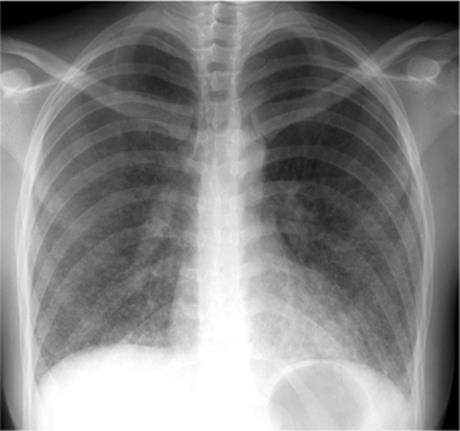

Focal opacity may be visible, especially when comparing one lung with the other on the frontal projection. On the lateral projection attention should be directed over the thoracic spine, the cardiac silhouette, and the retrosternal and retrocardiac regions, where faint opacity may otherwise escape detection (Figs. 5.1 and 5.2).

Figure 5.1 Opacity in pneumonia. (A) Posteroanterior and (B) lateral chest radiographs: minimal right basilar opacity, much better seen on the lateral view overlying the heart (P).